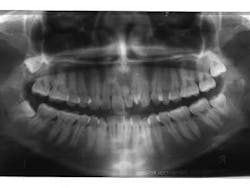

Month 0-3 I like to start all my orthodontic cases off with a light round nickel titanium wire such as an 014N or 012N. While in this wire, I used some elastomeric chain to help align and rotate the teeth.Month 4-10 I continued to level the teeth and begin to reposition brackets on a 18X25 heat-activated NiTi wire based on a panoramic X-ray that I like to take to help me with root positioning.Month 11-16 Progress to a stainless steel 19x25 wire for more tooth torque and better bracket engagement.Month 16-18 Finishing on a 018SS. I don’t have much wire-bending skills, so I mostly move brackets and am capable of only some simple step bends.